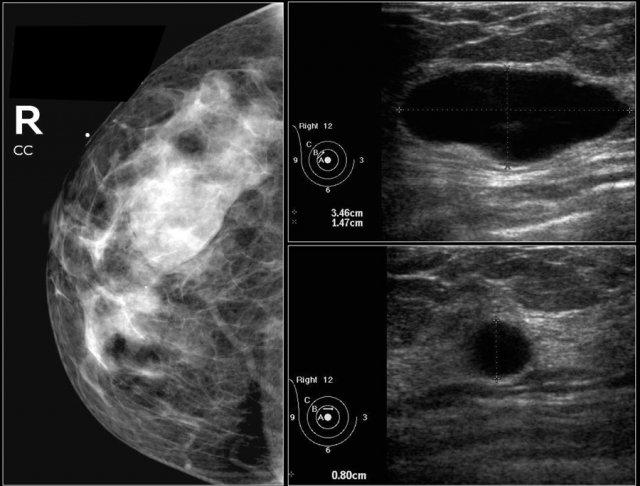

Đây là những hình ảnh mà bạn đã xem trước đó.

Đây là hình ảnh của một bệnh nhân có tổn thương mới phát hiện khi tầm soát.

Trên siêu âm phát hiện một hạch bạch huyết trong tuyến vú, nhưng chúng tôi không chắc liệu đây có phải là cùng tổn thương với khối trên nhũ ảnh hay không.

Tiếp tục xem các hình ảnh nhũ ảnh sau khi tiêm thuốc cản quang.

Thuốc cản quang được tiêm vào hạch và chụp nhũ ảnh lại.

Qua đó, chúng tôi có bằng chứng xác nhận rằng khối trên nhũ ảnh chính là hạch bạch huyết trong tuyến vú, vì khối trên nhũ ảnh có chứa thuốc cản quang.